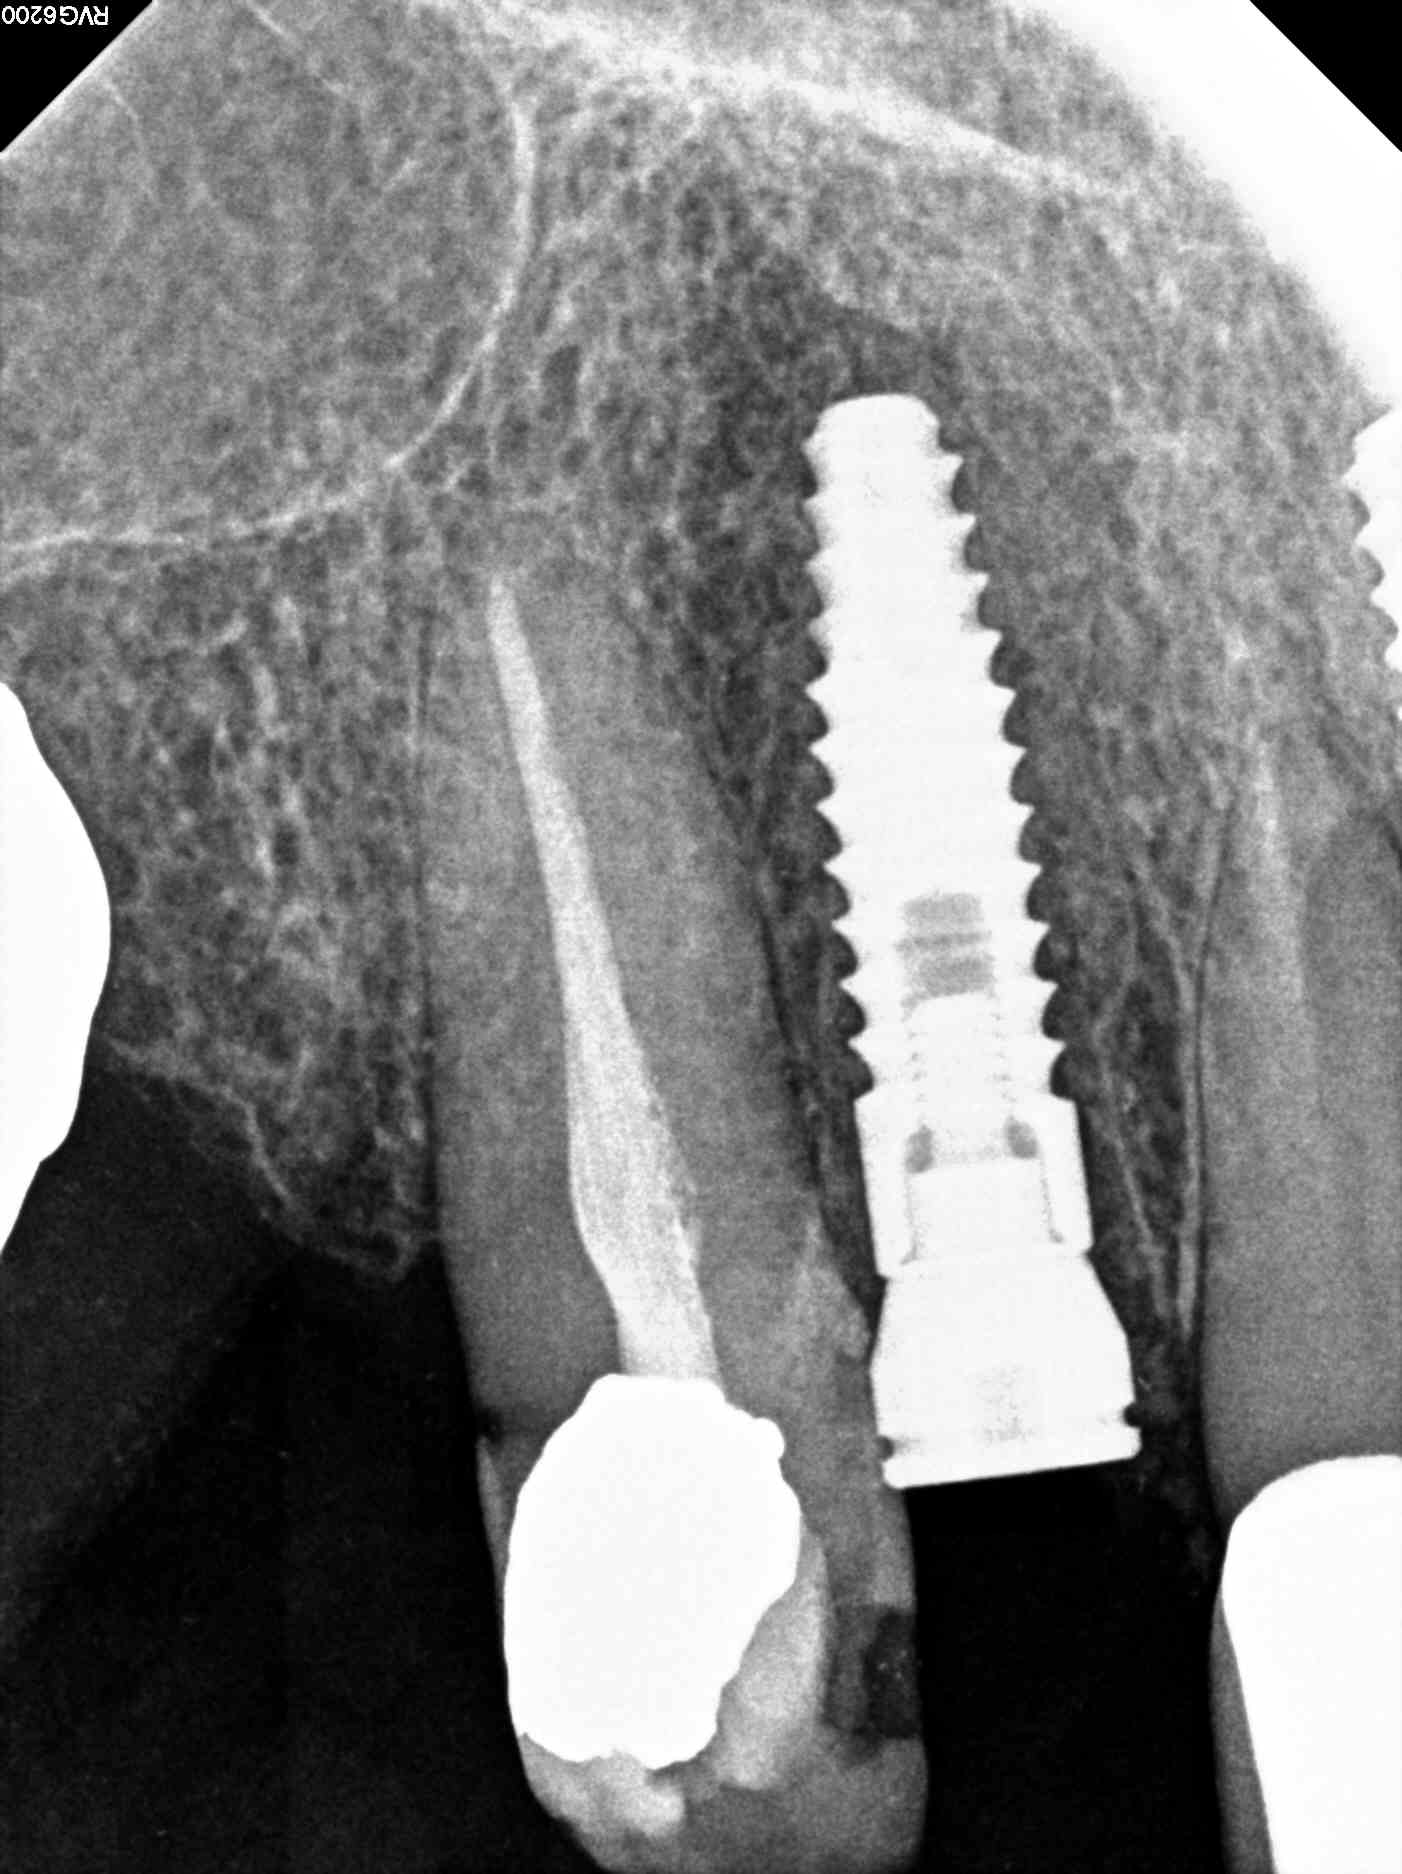

Our geriatric patient had a heavily restored dentition and things were falling apart for her. She needed something both durable and reliable. For teeth #7 and #9, both non-restorable, the best option was immediate dental implant placement and temporary crowns. The teeth were atraumatically extracted and based on the CBCT that was done at our office it was deemed that her bone quantity and quality was sufficient for her to get immediate implants. The case is still in progress and we attached X-rays in this blog of the immediate post-op result. She will be returning in 4 months for final impressions for her dental implants.